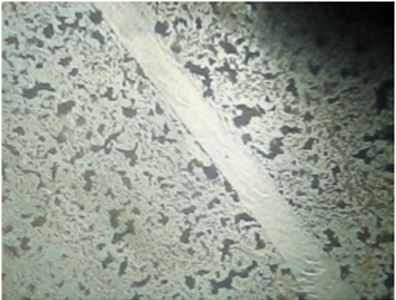

In-vitro scratch assay

Percentage (%) of cells that moved in the direction of the wound and helped it close microscopically images representing the In vitro wound healing nature of Sample: L929 cells were incubated in presence or absence of Samples and standard drug Cipladine and images were captured at 48 hours. According to images and results Sample showed Moderate activity Percentage (%) of cells that moved in the direction of the wound and helped it close.

Figure 2: Normal Morphology of L929

Control - Wound Scratch                                       After 48 hours - Control

Standard - Wound Scratch (Cipladine)                 After 48 hours - Standard (Cipladine)

Sample - Wound Scratch                                 After 48 hours - Sample

Table 2 Percentage (%) of Cells Reduction in Wound Closure.